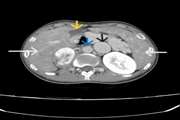

Massive hemothorax following CT-guided lung biopsy: A rare iatrogenic complication managed conservatively 1404/12/06 - 11:42